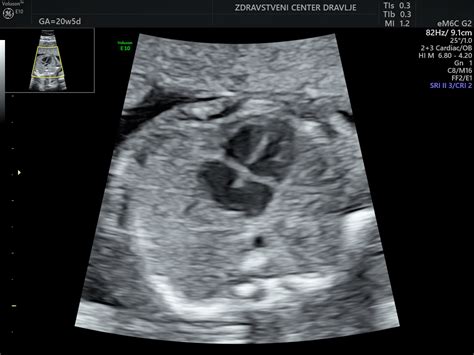

20. teden: Plod je velikosti banane, povprečne dolžine 19,7 cm in teže 260 g. Notranji organi so že na svojem mestu kot pri odraslem. V tem času se običajno opravi morfološki ultrazvočni pregled ploda, ki oceni pravilni razvoj ploda, ter določi lego posteljice. Polovica nosečnosti je mimo. Velikost maternice je do popka.